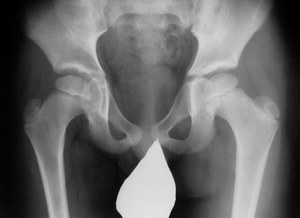

Диагностирование болезни Пертеса

Самым главным исследованием, которое имеет решающих фактор при установке диагноза болезнь Пертеса, считается рентгенография тазобедренного сустава. Во время подозрений на эту болезнь производятся не только снимки в классических проекциях, но и

снимки в проекции Лауэнштейна

. Рентгенологическая картина будет зависеть от выраженности и этапа заболевания. Есть разные рентгенологические классификации, самыми распространенными из которых считаются классификации Сальтера-Томсона и Кэттерола.

Классификация Кэттерола:

- Первая группа. Рентгенологические симптомы болезни Пертеса неярко выражены. Определяется незначительный дефект в субхондральной или центральной области. Бедренная головка имеет нормальную форму. Линия перелома не определяется, отсутствуют изменения в метафазе.

- Вторая группа. Не нарушены очертания головки, на рентгенограмме заметны склеротические и деструктивные изменения. Определяется формирующийся секвестр, существуют признаки фрагментации головки.

- Третья группа. Головка почти полностью деформирована и поражена. Определяется линия перелома.

- Четвертая группа. Головка полностью поражена. Определяются изменения вертлужной впадины и линия перелома.

Классификация Сальтера-Томсона:

- Первая группа. На рентгенограмме в проекции Лауэнштейна определяется лишь субхондральный перелом.

- Вторая группа. Не изменена наружная граница головки, на всех снимках заметен субхондральный перелом.

- Третья группа. Субхондральный перелом находится на наружной области эпифиза.

- Четвертая группа. Субхондральный перелом полностью находится на всем эпифизе.

При сомнительном диагнозе на первом этапе заболевания иногда делают МРТ тазобедренного сустава для более четкой оценки состояния мягких тканей и кости.